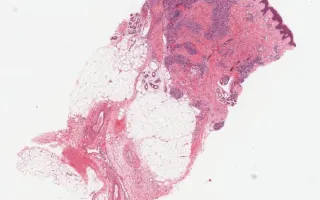

Blood vessels, tufted hemangioma, H&E stain

Tufted hemangioma

13 month old male infant with a tumour on the shoulder.

Tufted angiomas are benign vascular lesions which often occur on the neck or shoulders of children or young adults. Microscopically, they are comprised of nodules of tightly packed capillaries which may involve the dermis and superficial subcutis. Crescentic cleft-like vessels or semilunar lymphatic channels are generally seen at the periphery of some of the capillary tufts (nodules). These vessels are lined by unremarkable endothelial cells (CD31 positive) and surrounded by pericytes (smooth muscle actin positive). D2-40, a marker of lymphatic endothelial cells, is expressed in the crescentic cleft like vessels, but the proliferative capillaries are negative. The capillary lumina are not readily evident in many areas. GLUT-1 was negative in this case; it is positive in juvenile hemangiomas.

This slide shows H&E stain, see Related Content for CD31, D2-40, and SMA stains.